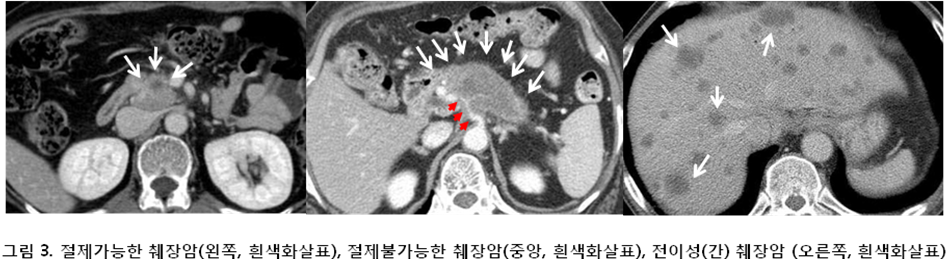

일반적으로 상복부불편감이 있을 경우 간편하고 부작용이 전혀없는 복부초음파검사를 많이 시행합니다. 하지만 췌장은 복부 깊숙히 자리잡고 있어 초음파로 췌장 전체를 자세히 관찰하기는 매우 어렵습니다. 대부분의 환자의 경우 복부 전산화단층촬영 (CT) 등의 영상 진단을 얻음으로써 진단 과정이 시작됩니다. CT에서 절제 가능하다고 판단되는 경우는 종양이 췌장에 국한되고, 중요 동맥의 침범이 없는 경우입니다 (그림 3). 완전절제 가능하다고 판단되는 경우에는 수술 전 조직 검사 없이 절제술을 바로 시행합니다.

CT에서 절제 가능성을 판단하기 어려울 경우 자기공명영상검사 (MRI), PET-CT검사 혹은 내시경 초음파 (EUS)를 이용하여 수술 가능성 여부를 결정을 하게 됩니다. PET-CT검사는 췌장염과의 감별 혹은 타장기 전이가 의심될 경우 시행하기도 합니다. 내시경 초음파검사는 의식하진정상태 (소위, 수면내시경)에서 위내시경검사와 동일하게 시행합니다.

환자의 전신 상태가 수술을 받지 못할 정도로 안 좋은 경우나, CT 또는 MRI검사 결과 절제 불가능한 경우, 간 또는 복강, 기타 장기에 전이가 있는 경우에는 조직 검사를 시행하여 췌장암임을 확진 한 후 치료 계획을 세우게 됩니다. 조직 검사는 신체 외부에서 복부 초음파나 CT의 도움을 받아 시행하거나 내시경검사 (내시경 초음파포함)를 통해 시행합니다.